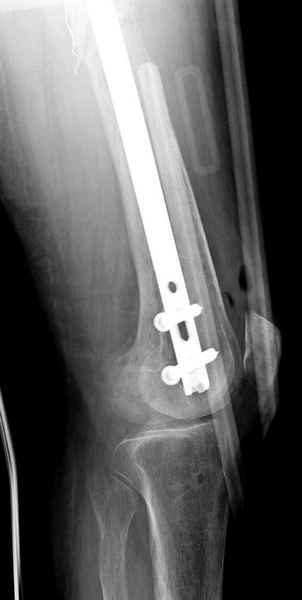

С минимальным рассверливанием и ретроградным методом провели остеосинтез бедра 12 мм гвоздем. (17-20)

Кровопотеря во время операции меньше 100 мл.